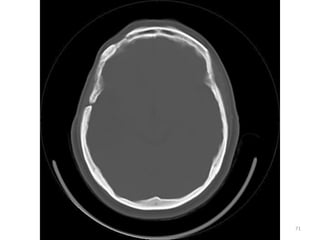

CORTES FOSSA POSTERIOR

SUPRA TENTORIAL

IMAGENS ÓSSEAS